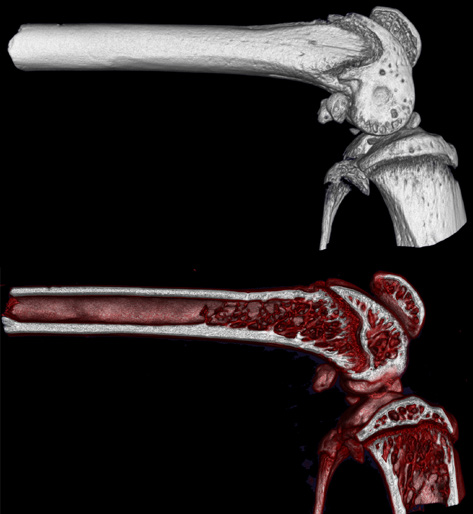

CosmoScan GX IIIは特に高い空間分解能を持ち、5µmまでの解像度と2.9µmのピクセルサイズ(FOV:8mm)を誇ります。これにより小さい骨の細かな解剖学的構造を含むex vivoサンプルの高品質な画像が得られます。

- 空間分解能 = 5µm 最小ピクセルサイズ = 2.9µm